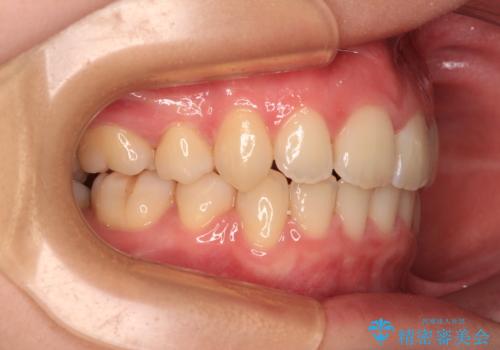

口の閉じにくさが改善され、横顔のシルエットも大幅に改善されました。

- 前歯のデコボコと突出感を気にして来院された患者様です。

上下左右第一小臼歯4本を抜歯して、積極的に口元を引っ込めるよう、ワイヤー装置にて矯正治療を行うこととしました。